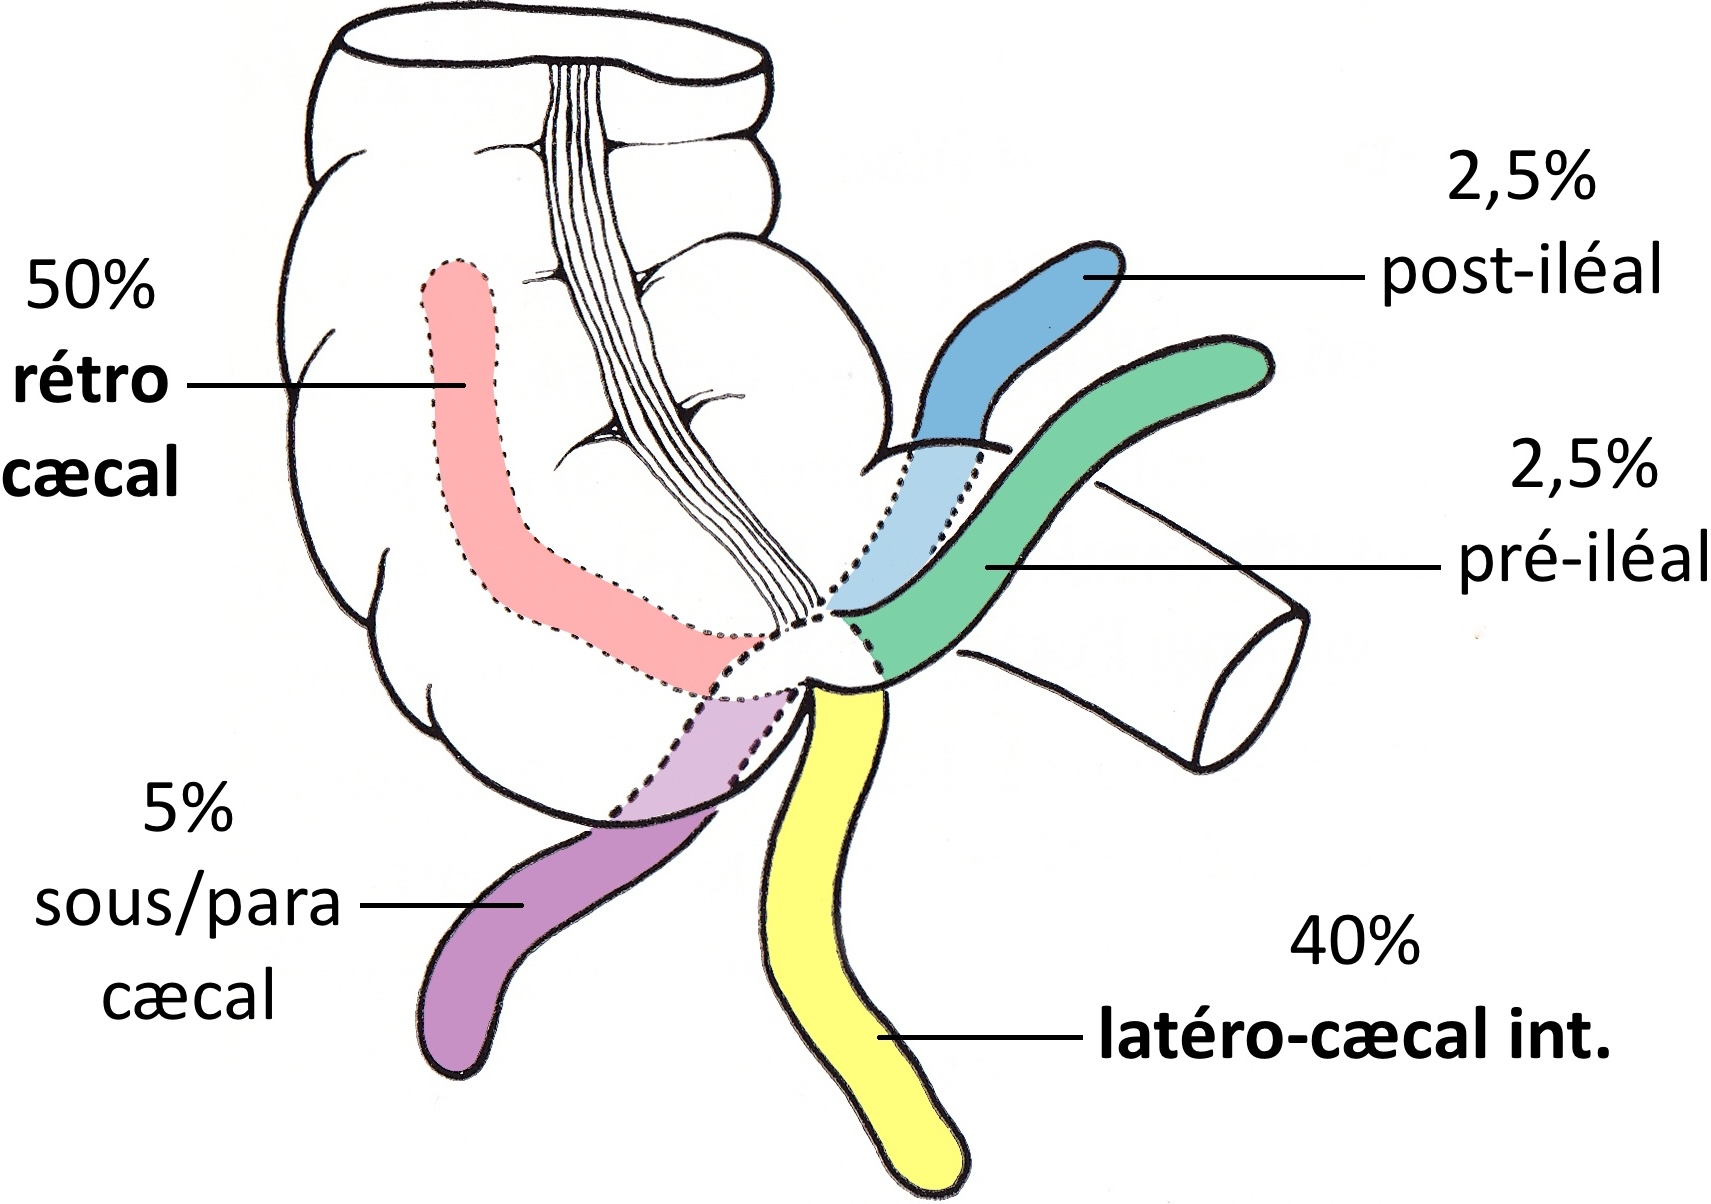

invagination iléo-iléale = plutôt > 2a

- vomis bilieux NNé < S2 à ventre plat, 80% < 1 an mais peut survenir à tout âge

- complique une mésentère commun incomplet (malrotation intestinale)

signe du tourbillon => PEC chirurgicale immédiate

écho non contributive / négative => opacification digestive haute